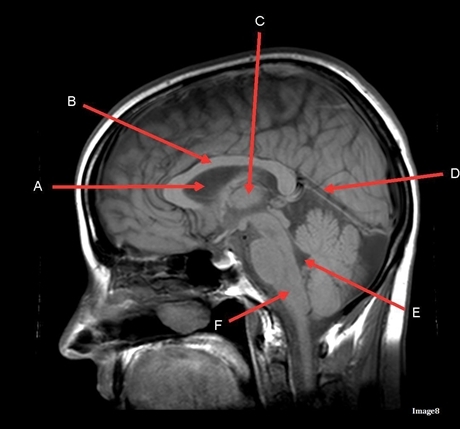

Image weighting and axis

T2 Flair

Sagittal

A

Genu Corpus Callosum

B

Splenium Corpus Callosum

C

Pons

D

Cerebellum